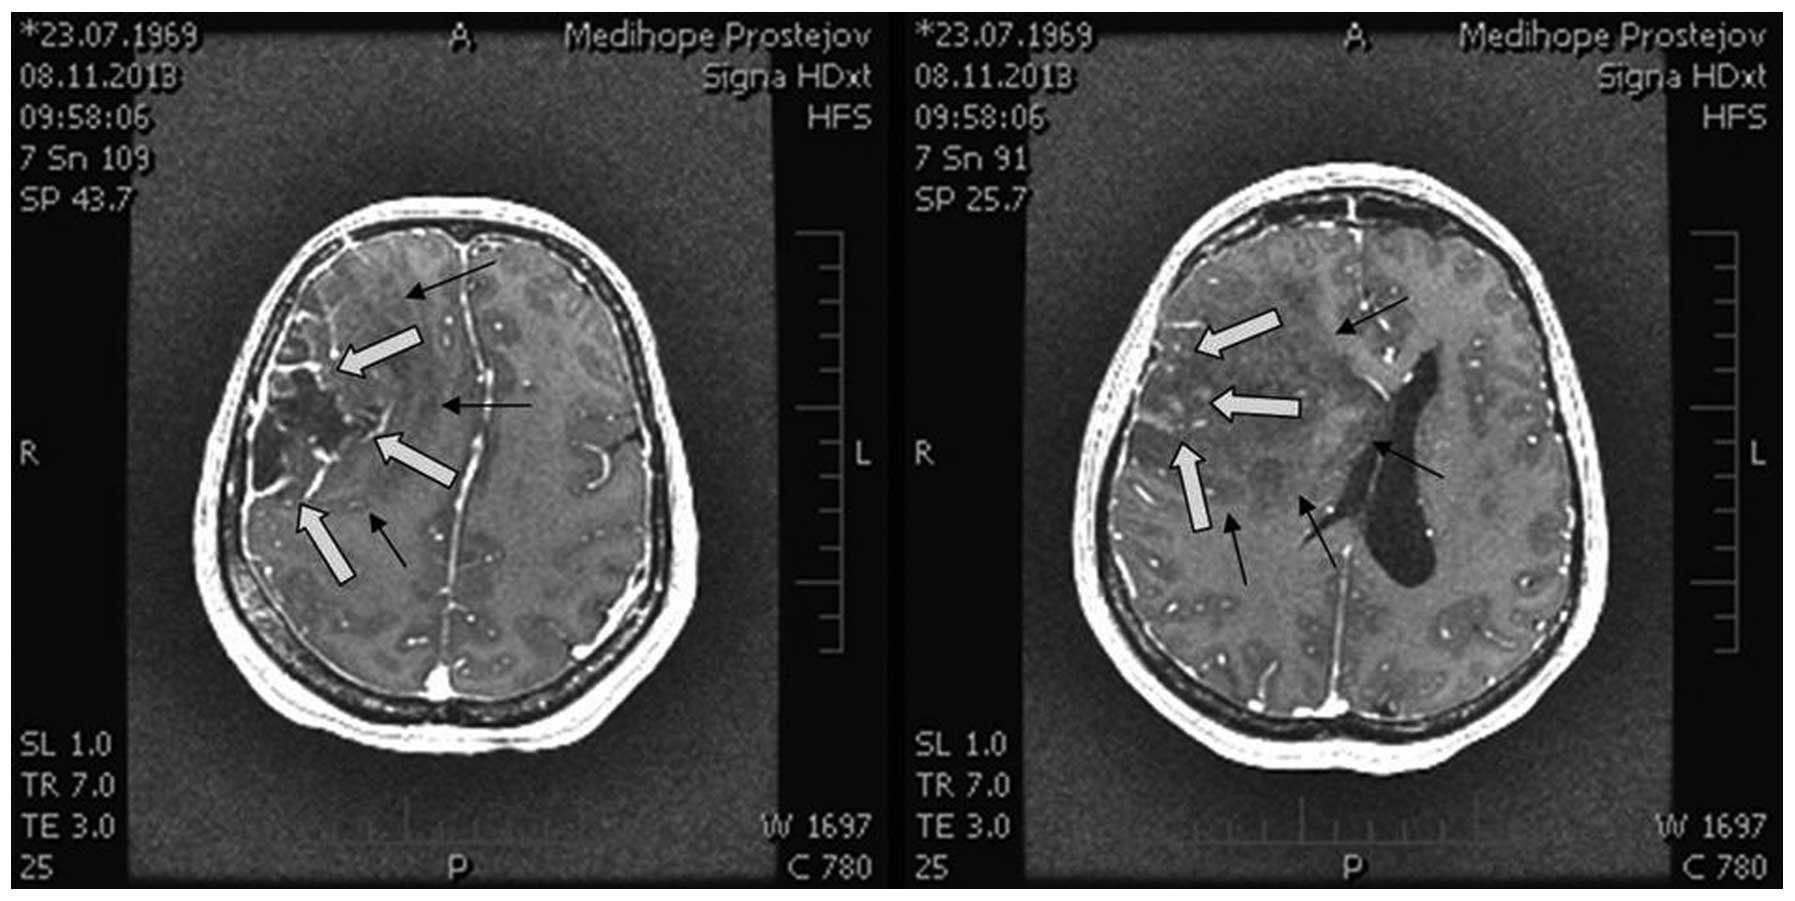

Extirpation of a multicomponent tumor was performed. On the surface there was a component corresponding with high-grade gliomas changing quite sharply into a low-grade glioma in the central section. Tumor extirpation was performed using an operating microscope, navigation system SonoWand and cavitron ultrasonic surgical aspirator. The border of a low-grade component was not visible against surrounding tissues. By contrast, it was well visible in the sono image and the real-time imaging during the extirpation of this section of tumor aided with the assessment. Thus, it was possible to achieve radical resection without post-contrast enhancement in the follow-up MRI scans. Surgery was executed without any complications. Left-sided hemiparesis regressed. The tumor was removed radically, there was no evidence of disease on the follow-up MRI scans and the patient did not experience any significant complications (Fig. 3).

Figure 3.

Postoperative magnetic resonance imaging coronar and sagital scan (high- and area low-grade areas).